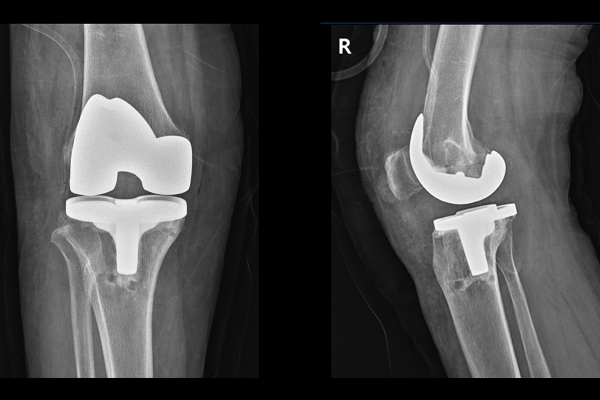

기존 인공관절을 잘 제거하고서, 3D 기술을 통해 환자분에게 맞춤형으로 제작된 인공관절로 교체해드렸습니다. 전치환술 후 X-RAY를 보면 잘 치환된 것이 확인됩니다.